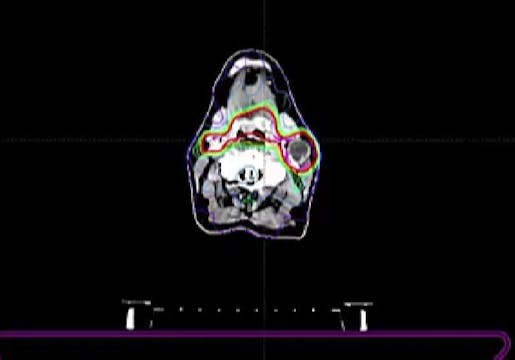

06/30/2025 - Dr. David Sher - Radiation Oncology - Head & Neck

Chartrounds US - Head and Neck Cancer